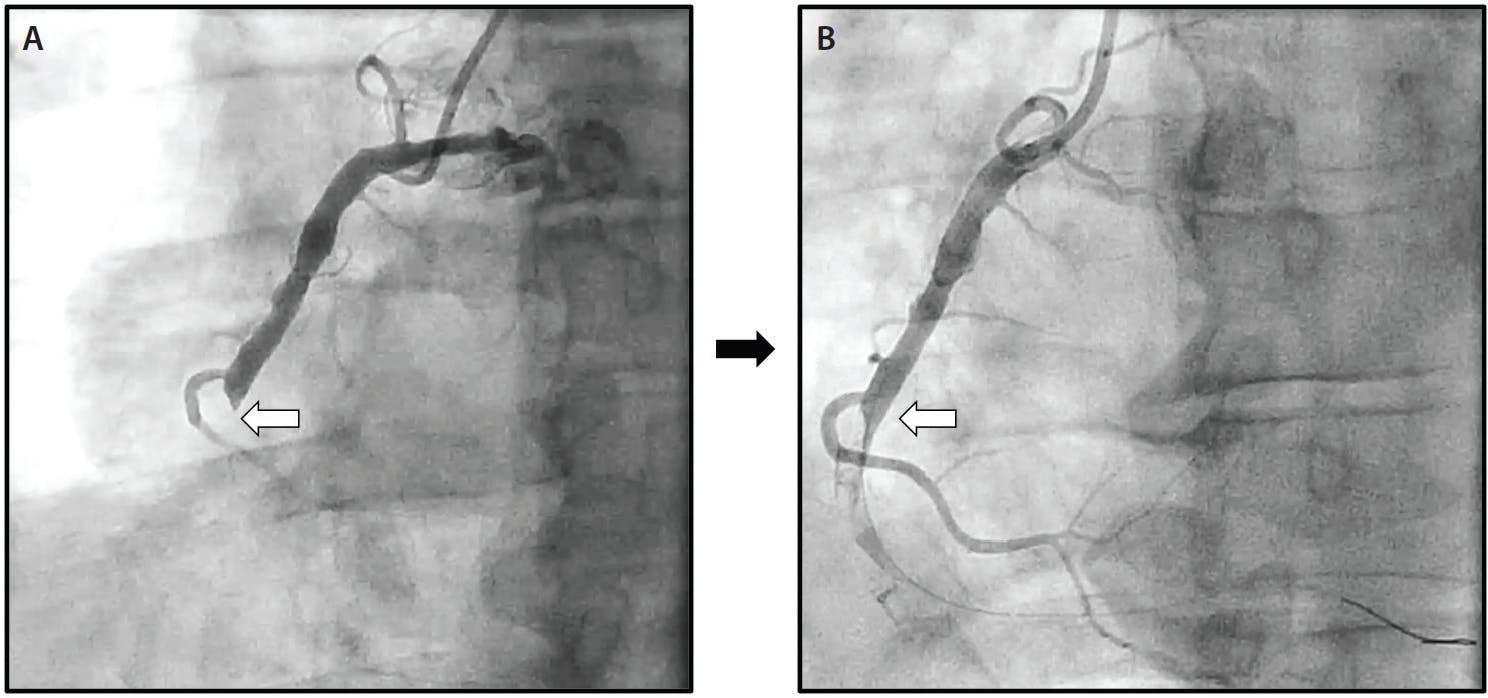

Upon arrival to the cardiac catheterization laboratory, transradial arterial access was obtained, and a 6-F Glidesheath Slender Sheath® (Terumo Interventional Systems) was introduced into the right radial artery. A 5-F Tiger catheter (Terumo Interventional Systems) was used to engage and image the left and right coronary arteries. Coronary angiography demonstrated nonobstructive coronary artery disease in the left coronary arteries with a 100% acute thrombotic occlusion at the mid segment of the RCA (Figure 1). At this point, intravenous cangrelor was initiated and the RCA was easily wired using a Runthrough NS Extra Floppy® wire (Terumo Interventional Systems). After predilating with a 2.0- X 10-mm semicompliant balloon, extensive thrombus was visualized on angiography with restoration of only TIMI 1 flow. At this point, given the presence of significant thrombus burden throughout the RCA and persistent chest pain, the decision was made to perform mechanical power aspiration using the Indigo System CAT RX. Two passes were made, aspirating a total of 40 mL of blood with extensive thrombus (Figure 2). There was a significant improvement in flow, distally limited by the presence of a small, persistent, distal RCA thrombus. Two drug-eluting stents (DESs; 3.5- X 38-mm) were placed followed by proximal postdilatation with a 4.0- X 15-mm noncompliant balloon. Final angiography and intravascular ultrasound demonstrated excellent stent expansion and apposition, resulting in restoration of TIMI 3 flow to the distal RCA. The patient remained hemodynamically stable with resolution of his chest pain. Radial arterial hemostasis was achieved using a TR Band® (Terumo Interventional Systems). The patient was discharged 2 days later.

Figure 1. Coronary angiography demonstrated a 100% complete thrombotic occlusion of the mid-RCA (white arrow) (A). Balloon angioplasty restored minimal flow to the vessel distally (B).

Figure 2. Two runs of the Indigo System CAT RX significantly improved flow distally (A). PCI was then performed using DESs (3.5 X 38 mm), resulting in an excellent final angiographic result with brisk flow to the distal RCA (B).